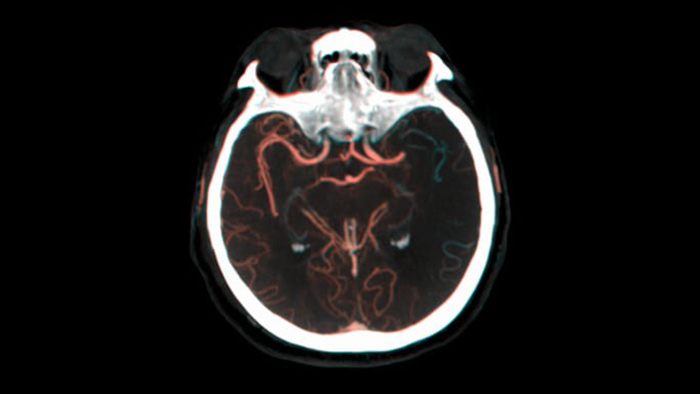

КТ-подобная визуализация

SmartCT Soft Tissue выполняет КТ-подобную визуализацию мягких тканей и дополняет диагностику инсульта тремя способами. Технология бесконтрастного сканирования помогает выявить ишемические изменения на ранних стадиях. Сканирование ранней фазы помогает определить проксимальную окклюзию. Сканирование поздней фазы с усилением контраста направлено на обнаружение коллатералей.

SmartCT Vaso IV

Провекра положения и длины тромба

SmartCT Vaso позволяет проводить визуализацию за пределами тромба с помощью перипроцедурного создания изображений дистальных сосудов при ишемическом инсульте. SmartCT Vaso — это метод сбора данных, основанный на получении КТ-изображений с помощью конического пучка и внутриартериальной инъекции контраста. Технология позволяет проводить визуализацию за пределами тромба с помощью перипроцедурного создания изображений дистальных сосудов при ишемическом инсульте. При ретроградном наполнении становится видна структура сосудов до и после тромба. 3D-схема сосудов SmartCT Vaso может использоваться при визуализации устройств для извлечения тромба.

Смотреть наполнение коллатералей

Визуализация наполнения коллатералей

Технология Dual View для одновременного просмотра ранней и поздней фаз КТ-подобной визуализации способствует определению ишемической полутени и обеспечивает визуализацию наполнения коллатералей.